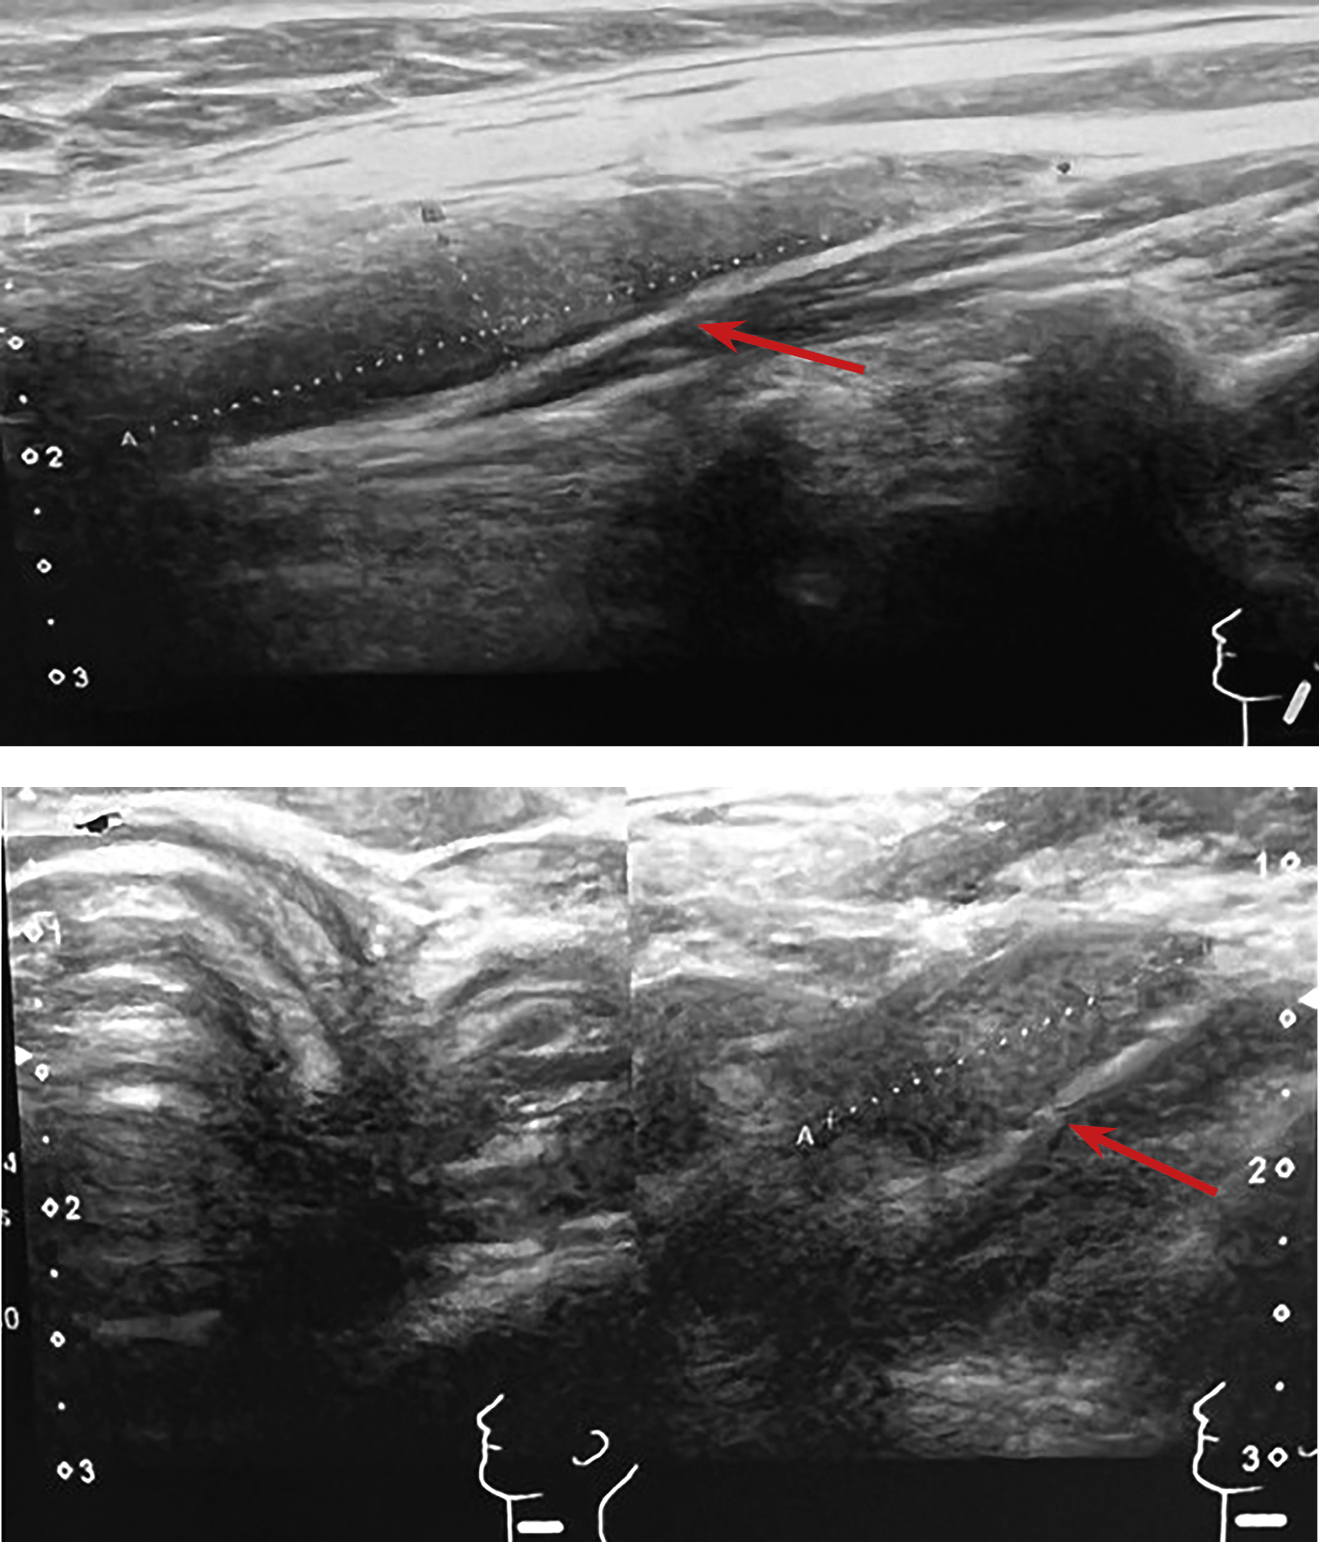

1. Рисунок 1. Ультразвуковое изображение образования в верхней трети шеи за внутренней яремной веной слева, в области бифуркации сонной артерии, характерное для аденомы ОЩЖ. | |